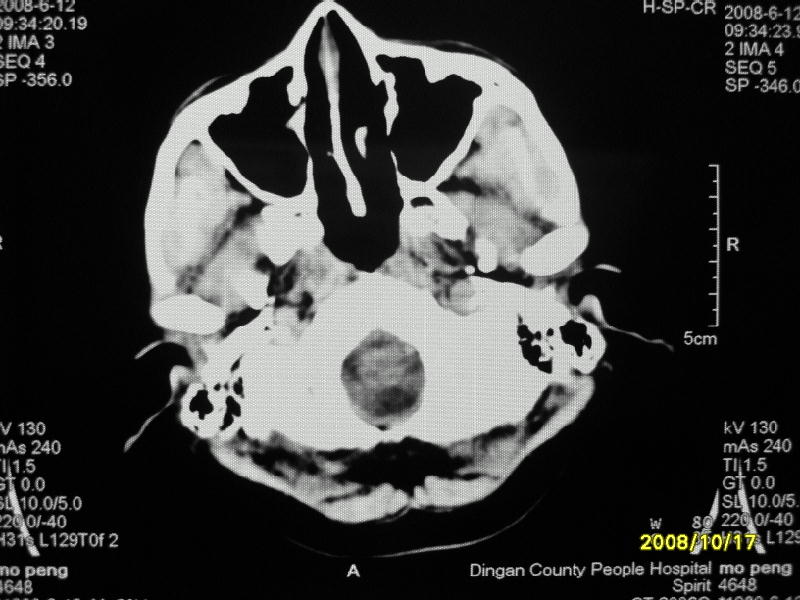

检查名称:     ct颅脑平扫           男     28岁

表现:左顶叶见斑点状致密影。边缘清,大小约0。3*1。0cm,余脑实质密度及灰白质结构示见异常。脑室系统大小,形态,密度未见异常。脑沟。脑裂。脑池未见异常密度影。中线结构无移位。

印象:左顶叶少许钙化灶

左顶叶见斑点状致密影。边缘清,大小约0。3*1。0cm,余脑实质密度及灰白质结构示见异常。脑室系统大小,形态,密度未见异常。脑沟。脑裂。脑池未见异常密度影。中线结构无移位。

印象:左顶叶少许钙化灶。